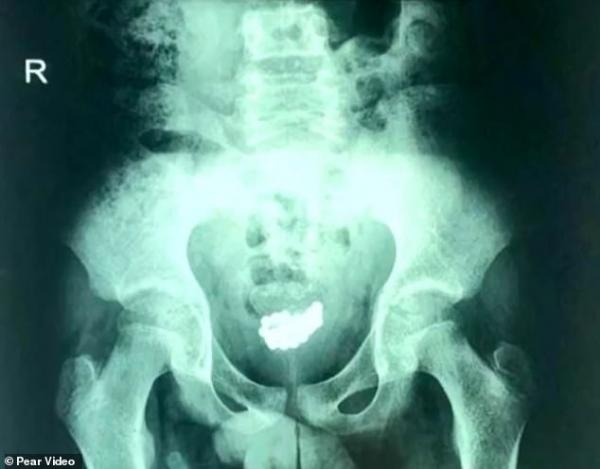

Kết quả chụp X-quang cho thấy bên trong bàng quang của cậu bé có rát nhiều bi nam châm.

Tại đây các bác sĩ đã tiến hành chụp X-quang cho cậu bé và tìm thấy một số lượng lớn bi nam châm (mỗi viên có đường kính 5 mm) co lại thành một cụm có đường kính khoảng 3 cm bên trong bàng quang của cậu bé.

Tổng cộng có 29 viên bi nam châm được lấy ra khỏi người cậu bé.